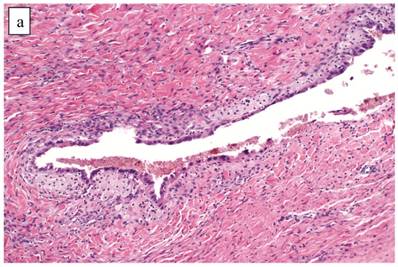

The clinicopathologic features with respect to age, stage, bilaterality, tumor size, and gross appearance are shown in Table 1. Histologically, the tumors contained a background of AF and exhibited greater glandular crowding as well as more variation in size and shape of glands, including cystic dilatation, compared with AFs (Fig. 2A). Occasional glands showed slightly more stratification of the epithelium (2-4 layers) but generally did not have substantial architectural complexity, such as papillary, solid, or cribriform patterns. The nuclei were mostly small, uniform, and flat to round but occasionally had mild nuclear enlargement and slight hyperchromasia; nucleoli, if present, were usually small (Fig. 2B).

Atypical proliferative (borderline) clear cell tumor. (A) The glands show a greater degree of crowding and variation in size and shape compared with clear cell adenofibroma. (B) The glands in many areas are lined by flat non-atypical cells. (C) Focal notable nuclear atypia is present in the glandular epithelium.

Only one case had mitotic activity (1 MF/10 HPFs). Notable nuclear atypia was focally present in 11 (27%) cases (Fig. 2C); however, such foci lacked associated stromal alterations and recognizable forms of invasion, such as an haphazard infiltration of glands, glandular confluence, mitotic activity within glands, or the conventional appearance of clear cell CA.